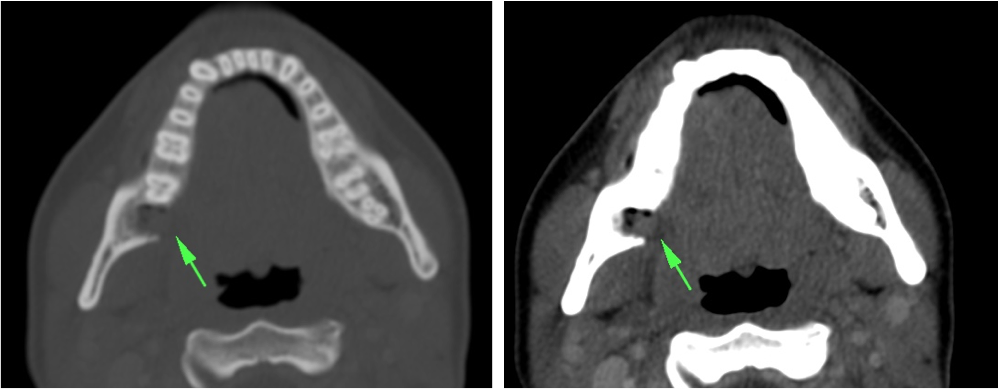

ESPACIO SUBLINGUAL Y SUBMANDIBULAR. ANGINA DE LUDWING:

Espacio sublingual:

Se sitúa inferior a la porción móvil de la lengua pero superior y medial al músculo milohioideo = Colecciones en esta localización son las denominadas sublinguales (las reconstrucciones coronales y sagitales son fundamentales). Contiene además a la glándula sublingual y una pequeña porción del aspecto superior de la glándula submandibular. Igual que en el espacio submandibular, las infecciones se manifiestan clínicamente por tumefacción, dolor, rubicundez y aumento de temperatura cervical. La mayoría son de origen dentario:

- Las que afectan a los dientes anteriores suelen limitarse al espacio sublingual, ya que sus raíces se quedan superior al milohiodeo.

- Las infecciones del 2º y 3º molar se suelen localizar en el espacio submandibular, ya que sus raíces se sitúan inferior a la inserción del milohioideo en la cara medial de la mandíbula (ver a continuación).

Espacio submandibular:

El espacio submandibular se sitúa inferior y lateral al músculo milohioideo. Es posterior al borde libre del milohioideo y comunica con el espacio sublingual (ver foto arriba). Contiene además la glándula submandibular, ganglios y a veces pueden localizarse quistes branquiales.

- Las infecciones del 2º y 3º molar se suelen localizar aquí. También pueden ser debidas a las supuración de adenopatías.

- Las infecciones de la glándula submandibular pueden confundirse con las de la parótida.

- Se produce aumento de tamaño, hiperdensidad e infiltración de la grasa adyacente. Cuando esto ocurre, se debe examinar el conducto de Wharton en busca de posibles cálculos.

- Otra forma de manifestación la constituye el flemón, con o sin celulitis y/o miositis, en estos casos se visualizan como masas hiperatenuadas, de bordes mal delimitados, con o sin engrosamiento e hiperatenuación de la musculatura, la piel y el tejido celular subcutáneo adyacentes.

Angina de Ludwing:

No es un absceso, es una celulitis multiespacial ya que afecta al suelo de la boca y los espacios sublingual y submandibular. Se manifiesta clínicamente por dolor, hinchazón, disfagia, fiebre y elevación de la lengua, puede asociar crepitación si se deben a microrganismos anaerobios. En la TC con contraste se observa:

- Realce y edema difuso de los componentes del suelo de la boca.

- Debe determinarse si existe colección susceptible de drenaje, permeabilidad de la vía aérea y presencia de aire secundario al crecimiento de microorganismos anaerobios.

- La infección causa elevación y desplazamiento de la lengua que puede cerrar la vía aérea (debe tenerse en cuenta a la hora de manejar estos pacientes antes de realizar la prueba).